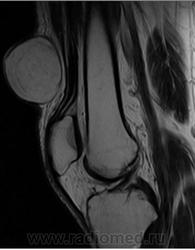

При осмотре атерома представляет собой опухолевидное образование округлой формы, мягкой консистенции размером от 5 до 40 мм и более. Кожа над атеромой обычно не изменена, однако в случае присоединения воспаления может иметь красноватый оттенок. Атерома подвижна вместе с окружающими тканями, безболезненна. Атерома может оставаться маленькой на протяжении многих лет, либо увеличиваться.

Иногда атерома сообщается с поверхностью кожи через небольшое отверстие, через которое могут отделяться атероматозные массы. Часто атеромы нагнаиваются, кроме этого, может происходить разрыв атеромы в подкожную клетчатку.